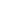

환자명 : 사OO

2025.05.26 업데이트

수술 후 촬영일자 : 2025.02.20